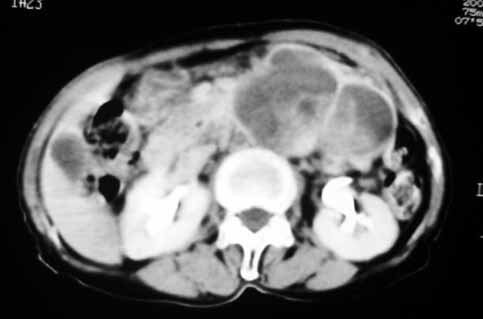

以下是引用天南地北在2007-4-30 17:42:00的发言:[br]增强扫描显示腹主动脉给包绕、推移。肿块不规则强化,[br]修正我在平扫的诊断[br]支持考虑:间叶源性肿瘤可能性大

以下是引用余辉在2007-4-30 18:01:00的发言:[br]病灶前方的条状增强影是什么?若是胰腺,位置似乎有点低,若是十二指肠,似乎又不诫该是那样强化,姑且将其看作胰腺吧,那么考虑来源于胰腺粘液囊腺瘤可能性大,其次考虑来源于肠系膜或者后腹膜的肿瘤如平滑肌肉瘤,异位嗜铬细胞瘤及淋巴瘤等。

以下是引用zyx168在2007-4-30 23:24:00的发言:[br]考虑:间叶源性肿瘤可能性大